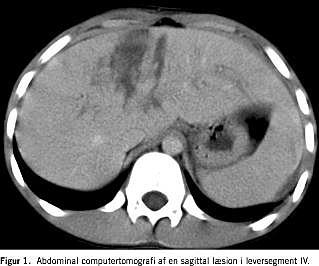

Patienten, en 11-årig dreng, blev nytårsaften ramt i abdomen af en ca. 1 m lang raket. Rakettens stativ faldt under affyringen, hvorefter raketten vendte sig i retning af patienten, der stod 10-15 m derfra. Raketten ramte ham i epigastriet, sprang tilbage og eksploderede derefter. Patienten havde abdominalsmerter resten af natten, hvorfor han blev bragt til skadestuen den næste dag. En objektiv undersøgelse viste en mindre ekskoriation i epigastriet, abdomen var blødt, men med direkte ømhed i epigastriet. Ved en abdominal ultralyd (UL)-skanning blev der fundet en væskeansamling bag galde- og urinblæren og svarende til milten. Der blev ikke fundet lever- eller miltlæsioner, og patienten blev indlagt til observation. Han havde et hæmoglobinfald og blev let tryklabil næste dag, hvorfor der blev foretaget abdominal computertomografi (CT), som viste en svær gennemgående sagittal leverlæsion, som næsten delte segment IV i to dele, desuden sås ekstravasation af kontrast (Figur 1 ). Patienten blev akut overflyttet til en specialafdeling, hvor der blev foretaget arteriografi. Ved denne kunne der ikke påvises pågående blødning. For at udelukke kolaskos blev der udført ultralydvejledt diagnostisk punktur, og den intraperitoneale væske var uden galdetilblanding. Abdominale UL-skanninger blev regelmæssigt gentaget under indlæggelsen og viste uændrede forhold. Patienten var stabil under resten af indlæggelsen og blev udskrevet til hjemmet otte dage efter traumet. Han var velbefindende ved en kontrol efter fem måneder.

Summary Liverrupture caused by recreational fireworks Ugeskr L&aelig;ger 2005;167:2066-2067. An 11-year-old boy was hit by a piece of firework in the epigastric area of the abdomen. He was admitted to hospital, and computed tomography (CT) showed a large central lesion of the liver, which had nearly parted the liver in two pieces. In addition, extravasation of contrast was found. Angiography was performed, and no ongoing bleeding was found. Diagnostic peritoneal aspiration did not show any sign of bile leakage. The patient was treated conservatively and was discharged eight days after the accident. He is well and free of symptoms at five months' follow-up.